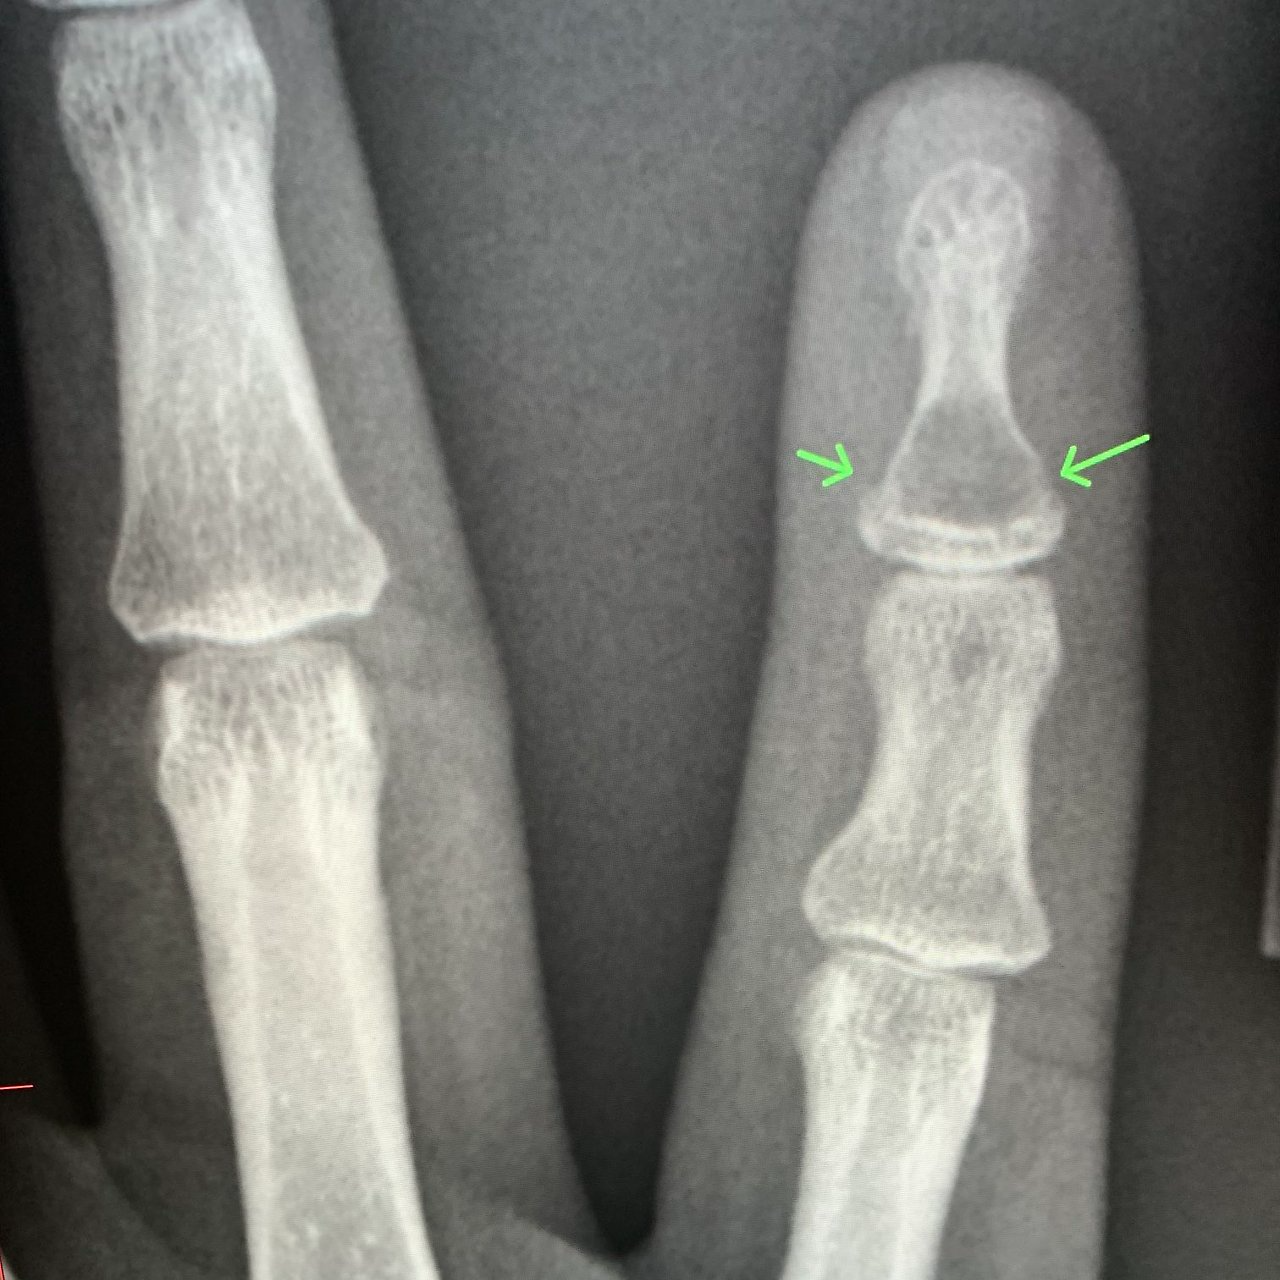

손가락 스플린트는 골절 위치에 따라 착용 각도와 형태가 달라집니다. 예를 들어 말단지 골절의 경우 손끝만 고정하는 단순 스플린트가 사용되며, 중간 마디나 관절 침범 골절의 경우 손가락 전체를 포함하는 고정이 필요할 수 있습니다. 스플린트 착용 기간은 대개 3-6주이며, 이후에는 점진적인 관절 운동이 병행됩니다.

손가락 뼈에 금이 가면 깁스 치료는 필요한가

많은 분들이 가장 궁금해하는 부분이 바로 “손가락 뼈에 금이 갔을 때도 깁스를 해야 하는가”입니다. 결론부터 정리하면, 모든 경우에 깁스가 필요한 것은 아닙니다. 손가락에 발생하는 미세 골절이나 비전위성 골절은 스플린트만으로도 충분한 안정성을 확보할 수 있는 경우가 많습니다.